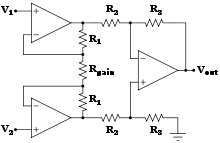

Biomedical sensors

In recent years biomedical sensors based in microwave technology have gained more attention. Different sensors can be manufactured for specific uses in both diagnosing and monitoring disease conditions, for example microwave sensors can be used as a complementary technique to X-ray to monitor lower extremity trauma.[13] The sensor monitor the dielectric properties and can thus notice change in tissue (bone, muscle, fat etc.) under the skin so when measuring at different times during the healing process the response from the sensor will change as the trauma heals.

- John G. Webster – professor emeritus at the University of Wisconsin–Madison, a pioneer in the field of instrumentation amplifiers for the recording of electrophysiological signals